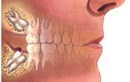

2. Cerrahi YöntemlerÇenenin yapısal bir problemi varsa, cerrahi müdahale gerekebilir. Aşağıdaki cerrahi yöntemler çenenin ileri alınmasında kullanılabilir: